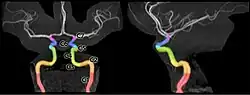

In clinical settings, however, usually the classification system of the internal carotid artery follows the 1996 recommendations by Bouthillier,[5] describing seven anatomical segments of the internal carotid artery, each with a corresponding alphanumeric identifier: C1 cervical; C2 petrous; C3 lacerum; C4 cavernous; C5 clinoid; C6 ophthalmic; and C7 communicating. The Bouthillier nomenclature remains in widespread use by neurosurgeons, neuroradiologists and neurologists.

The segments of the internal carotid artery are as follows:

- Cervical segment, or C1, identical to the commonly used cervical portion

- Petrous segment, or C2

- Lacerum segment, or C3

- C2 and C3 compose the commonly termed petrous portion

- Cavernous segment, or C4, almost identical to the commonly used cavernous portion

- Clinoid segment, or C5. This segment is not identified in some earlier classifications and lies between the commonly used cavernous portion and cerebral or supraclinoid portion.

- Ophthalmic, or supraclinoid segment, or C6

- Communicating, or terminal segment, or C7

- C6 and C7 together constitute the commonly used cerebral or supraclinoid portion.